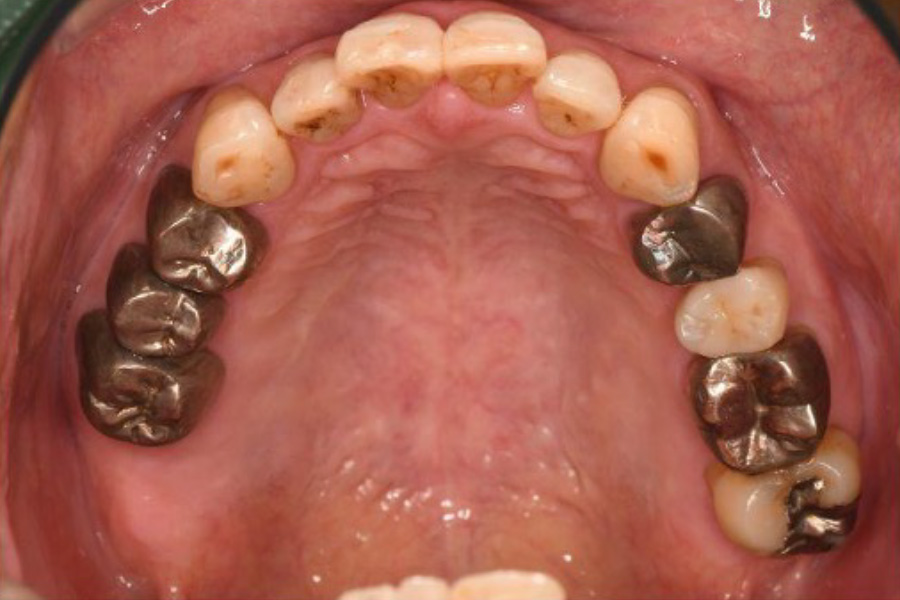

治療前

| 主訴 | 数年前から左下の一番奥の歯が噛んだときに痛む。 通院していた歯科で痛みはとれないがまだ抜かない方が良いといわれたが、ずっと痛いままなので不安になり来院。 |

| 治療内容 | 全顎治療:歯周病治療、抜歯、根管治療、 咬合治療・矯正治療、フルメタルクラウン(保険) |